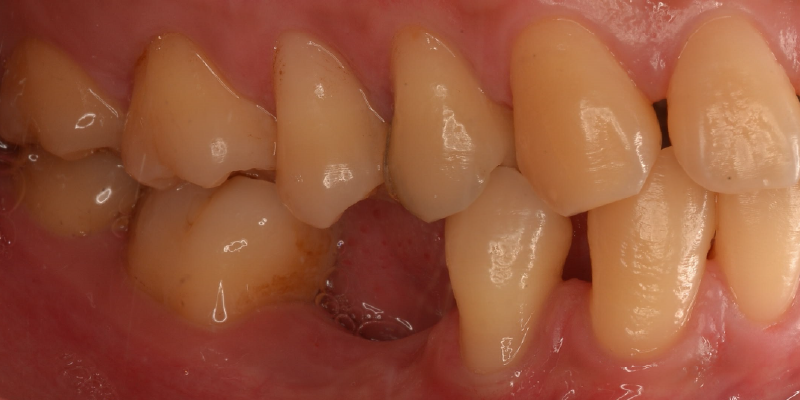

他の歯を削らない

インプラントは、失った歯の部分だけを治療するため、ブリッジのように周囲の健康な歯を削る必要がありません。大切な天然歯を守りながら、欠損部位だけを補えるのが大きな利点です。将来的な歯の寿命を考えたときにも、他の歯に負担をかけないインプラント治療は、優れた選択肢といえます。